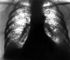

Рентгенологически фиброзно-кавернозный туберкулез легких характеризуется наличием одной или нескольких хронических каверн (участков просветления, окруженных плотной широкой кольцевидной тенью), сморщиванием окружающей легочной ткани, уменьшением объема легкого, смещением органов средостения, деформацией скелета грудной клетки, очаговым обсеменением в одном или обоих легких (рис. 21). При обострении появляются новые очаги обсеменения, свежие каверны и участки инфильтрации легочной ткани.

Хронические каверны чаще локализуются в I, II и VI бронхолегочных сегментах одного или обоих легких. В стенке хронической каверны выделяют 3 слоя: внутренний — некротический, средний — слой туберкулезной грануляционной ткани, наружный — соединительнотканный (рис. 18). В состав стенки входят облитерированные и дренирующие бронхи, варикозно-измененные сосуды. Наряду с хронической каверной определяются различной степени выраженности пневмосклероз, утолщение и склероз плевры (рис. 19), очаги отсева в прилегающей легочной ткани, эмфизема, бронхоэктазы. При прогрессировании процесса с бронхогенным распространением микобактерий туберкулеза поражаются бронхи, нижние отделы легкого и противоположное легкое. Возможны разрушение легкого, развитие казеозной пневмонии с многокамерными полостями распада, эмпиемой плевры, милиарной диссеминацией (в том числе с поражением мозговых оболочек). Нередко возникают легочное кровотечение, легочно-сердечная недостаточность, амилоидоз внутренних органов. Заживление хронической каверны может происходить путем рубцевания (рис. 20, а), формирования очага, или «выполненной» каверны (рис. 20, б), либо путем образования остаточной кистоподобной полости (рис. 20, в).